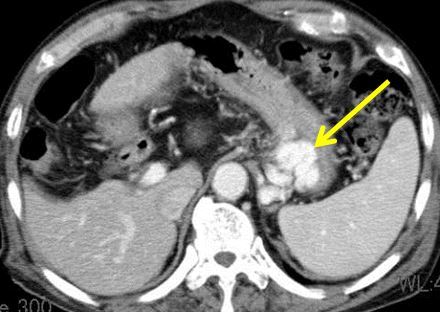

胃静脈瘤に対する経静脈的胃静脈瘤硬化療法(BRTO)

- 造影CTで胃静脈瘤がみられる(矢印)